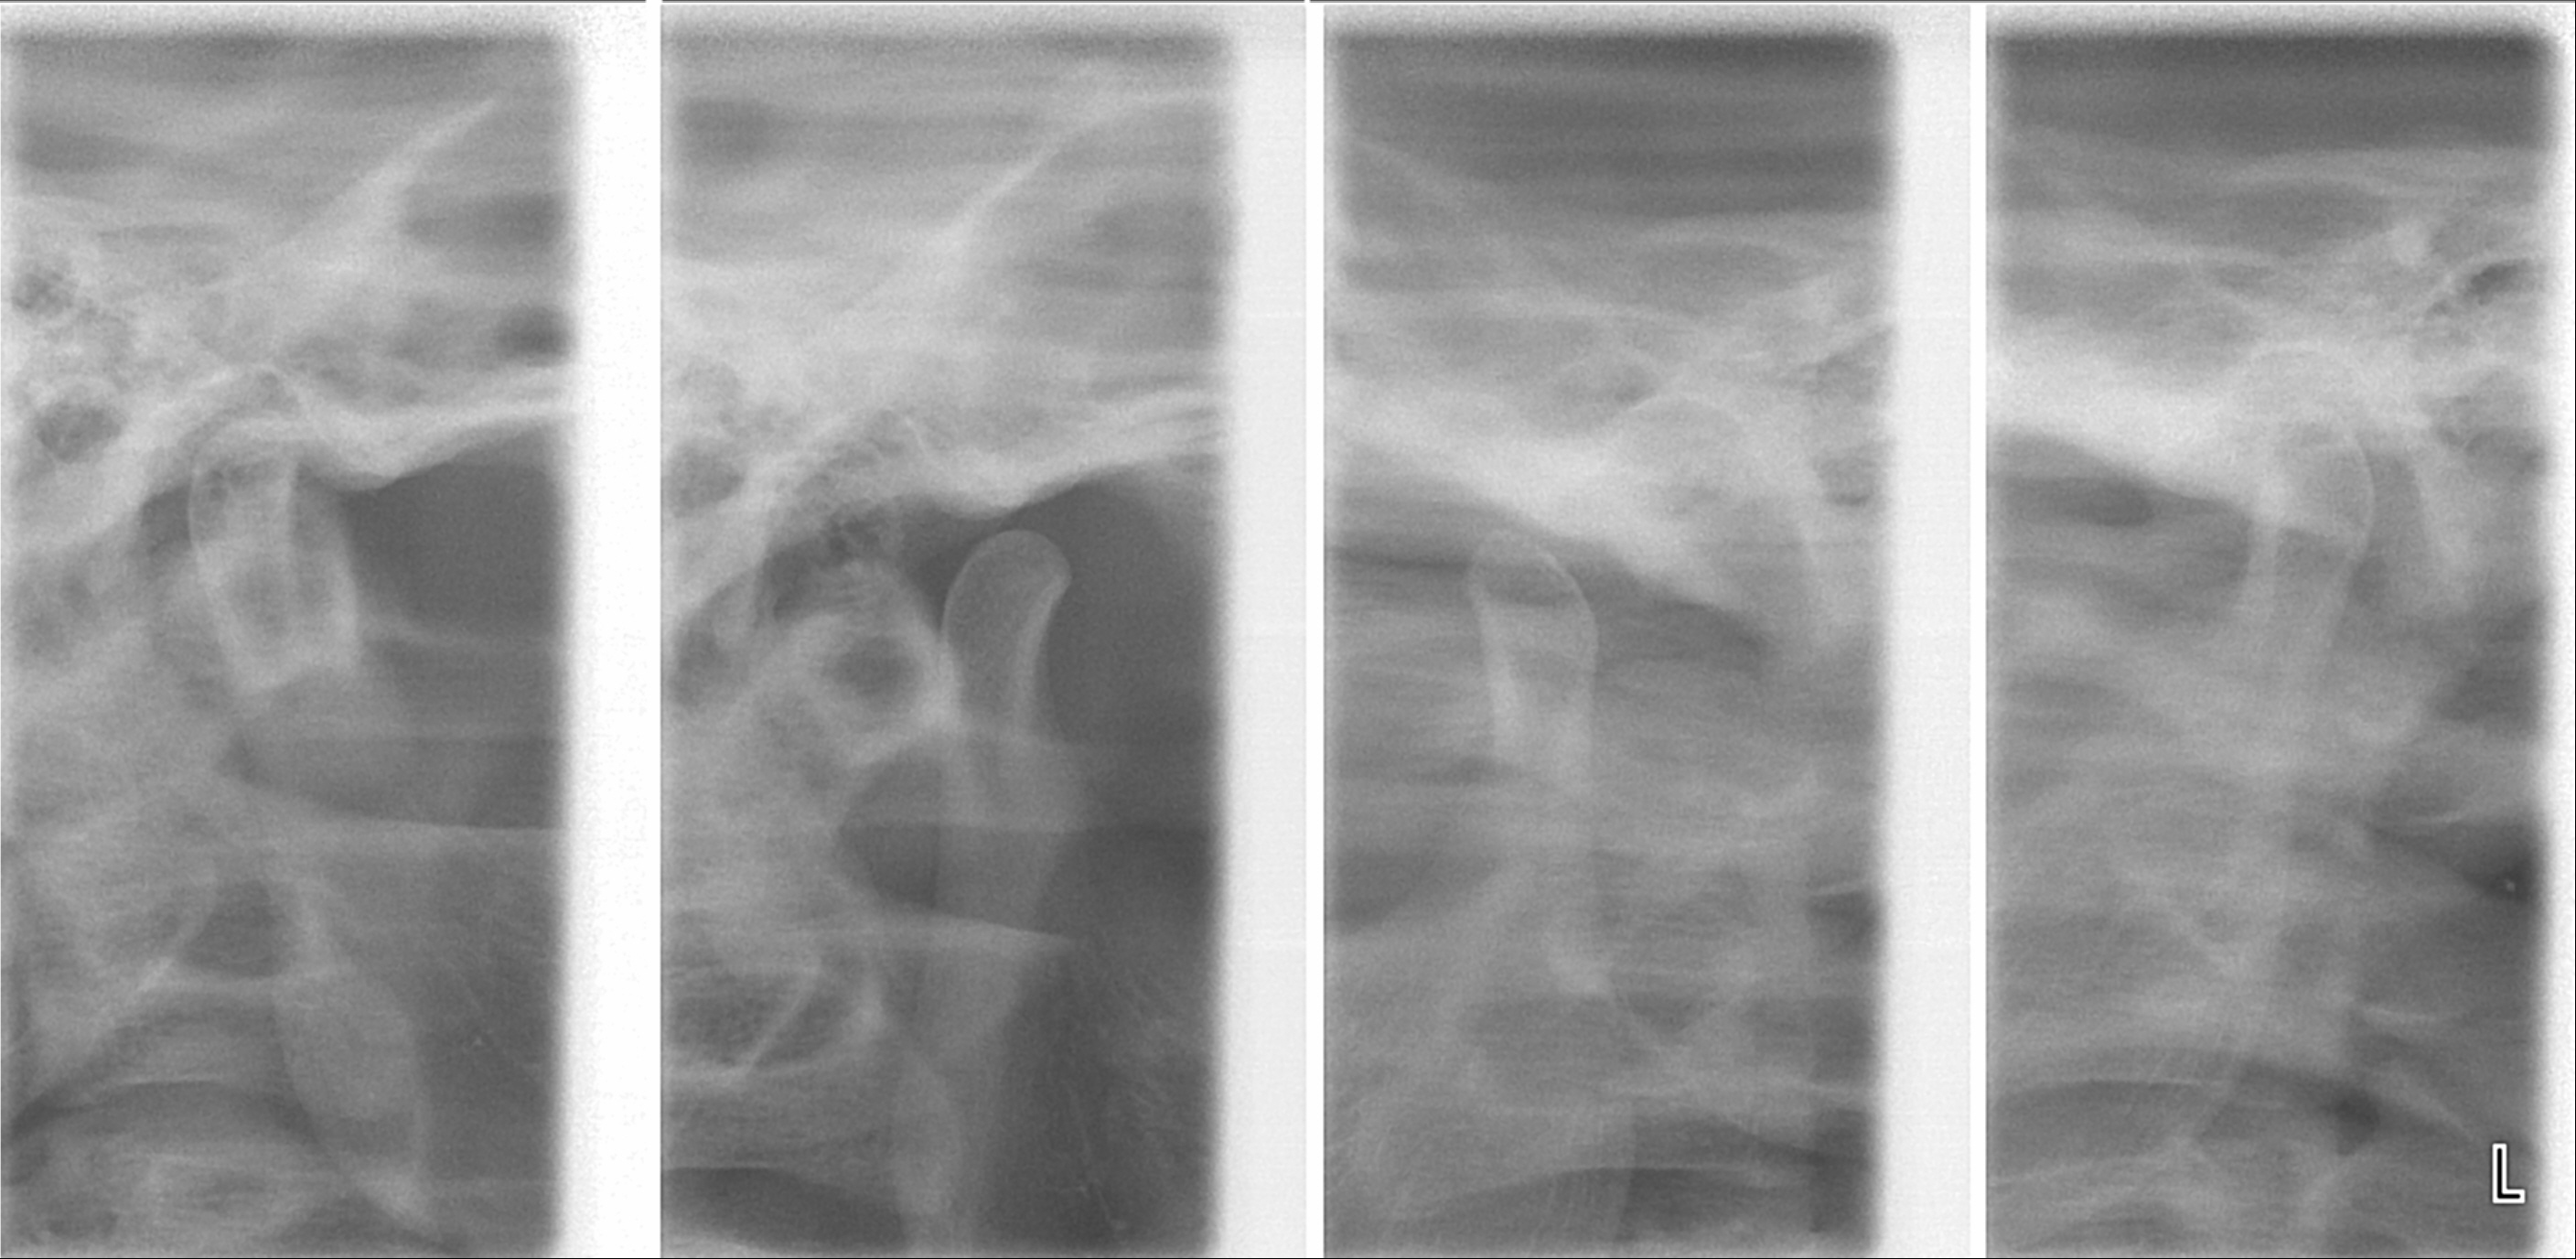

5. 3. 영상 검사

턱관절 장애(TMD) 진단에는 여러 영상 검사 방법이 사용된다. 임상 검사만으로 턱관절 상태를 파악하기 어려울 때, 영상 촬영은 임상 검사를 보조하는 역할을 한다.[48]| 검사 방법 | 설명 | 장점 | 단점 | 주요 사용 경우 |

| 일반 방사선 촬영 | 턱관절의 석회화된 부위(뼈)를 보여준다. | 연골 및 연조직은 보이지 않음, 주변 구조물이 겹쳐 보여 영상 판독이 어려움[48], 넓은 범위의 병변 진단에만 제한적 사용[49] | ||

| 파노라마 방사선 촬영 | CT나 MRI보다 저렴하고 간편함 | 영상 왜곡으로 인해 큰 골극이나 광범위한 침식만 감지 가능[49] | 턱관절 장애 초기 진단 | |

| 단층 촬영 | 턱관절의 단면 영상 제공 | 임상 검사만으로 얻을 수 없는 추가 정보 제공[50] | ||

| CT, CBCT 검사 | 턱관절 뼈 상태 평가 | 이상 부위 위치 및 범위 파악에 유용[52][53][54], CBCT는 기존 CT보다 방사선량 적음[55] | ||

| MRI | 턱관절 주위 연조직 촬영에 최적[56][53] | 디스크 위치 평가에 표준적 방법, 관절 내 퇴행성 변화 잘 보여줌[56], 신경 조직 평가에 유용[57], 괴사 및 부종 등을 방사선 노출 없이 평가[57] | 고가 장비 필요, 폐쇄공포증 환자, 심장 박동기나 금속 심장 판막, 강자성 이물질, 임산부 사용 불가[58] | 통증, 관절음, 탈구, 입 벌림 제한, 종양 의심, 골관절염 증상 등[57][58] |

| 초음파 영상(US) | 턱관절 내부 장애, 특히 디스크 위치 평가에 유용[59][60] | MRI 사용 불가 시 초기 검사에 유용, 저렴하고 실시간 영상 제공[52][53][59][60][61], 침윤술, 관절천자, 점성보충 시술 시 관절 공간 정확한 위치 파악에 사용[62] | 골관절증 진단에는 특이도 낮음[61], 염증성 질환자 삼출액 식별 가능[60][61][53] |